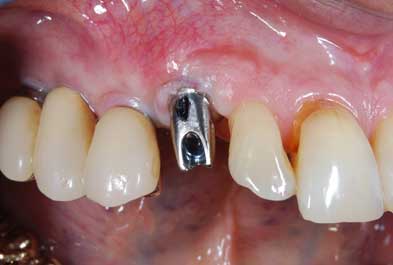

I denti irrecuperabili dell'arcata superiore ed inferiore del paziente di anni 65

sono stati sostituiti da 10 impianti, cioè protesi radicolari endo-ossee che sostengono le protesi fisse superiore ed inferiore.